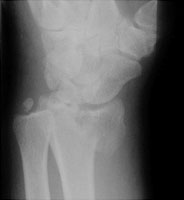

Reverse Barton Fracture

The reverse Barton fracture refers to an intraarticular fracture through the distal radius. Although it is similar in appearance to a Smith fracture, the Smith fracture is not intraarticular. The reverse Barton fracture involves the volar rim of the radius while the conventional Barton fracture involves the dorsal rim. The fracture is caused by direct trauma.

- Click on the image for a larger versionALateral radiograph of the wrist. This shows a displaced fracture of the volar rim of the radius.